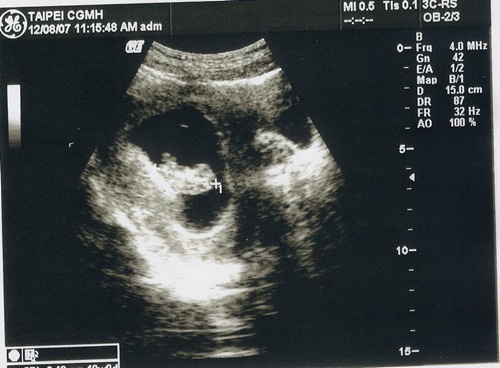

這次的超音波就不用畫圖說故事了吧 !!

再看不懂就只能說.. 你是火星來的嗎